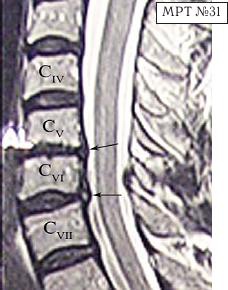

МРТ № 31 ![]() Он взял отпуск и поехал в Москву в довольно известную частную клинику. Прошёл курс лечения, который включал в себя «стандартный набор»: — мануальную терапию, с целью уменьшения (устранения) болевого синдрома, путём восстановления соотношений суставных поверхностей дугоотростчатых суставов в сегментах CV-CVI и CVI-CVII (устранение сублюксации); — массаж шейного отдела позвоночника (для расслабления мышц, улучшения кровообращения); — физиотерапию — магнитотерапию, инфракрасный лазер на воротниковую зону, с целью уменьшения воспалительных процессов и отёчности в поражённых тканях; — медикаментозную терапию — стандартный набор нестероидных препаратов, витамины и анальгетики; — физические упражнения на тренажёрах и лечебная физкультура для укрепления мышечного корсета позвоночника и выработки правильной осанки, придание связочно-мышечному аппарату необходимой гибкости с целью увеличения объёма движений в позвоночнике. После лечения действительно почувствовал себя лучше, работоспособность была восстановлена. Но, чтобы не утратить достигнутый результат лечения, следуя рекомендациям, полученным в московской клинике, он продолжил заниматься на тренажёрах. Даже приобрёл несколько универсальных (многофункциональных) тренажёров. Один установил дома, другой — на работе. Жизнь вошла в привычное русло. Боли в шее периодически возникали, но проходили после занятий на тренажёре. К медикаментам прибегал в редких случаях. Так продолжалось практически год, пока не появилась боль в левой руке и онемение IV и V пальцев. Занятия на тренажёре только усиливали боли, а лекарства практически не действовали. В связи с чем он был вынужден опять обратиться в ту же клинику. После лечения (практически по той же схеме) боли уменьшились, но полностью не прошли, онемение усилилось. Через некоторое время появилась субфебрильная температура (37–37,2 °C), общая слабость, частые головные боли, головокружения. По жалобам и ощущениям с его слов: «На голову надели будто тесную шапку и она сдавливает. А в голове туманность какая-то, мысли путаются, на чём-то сосредоточиться практически невозможно. Порой забываю, что минуту назад делал. Такое ощущение, что в голове полно посторонних мыслей: только от одних отделаюсь, как появляются другие» и так далее. Естественно, он вынужден был опять обратиться в медицинское учреждение, где ему повторно сделали МРТ (№ 32). ![]() После обследования у него было обнаружено: — абсолютный стеноз спинномозгового канала шейного отдела позвоночника с полным блоком ликворных путей и сдавлением дурального мешка спинного мозга на уровне сегментов CV-CVI и CVI-CVII; — в сегменте CV-CVI — значительный спондилёз, гипертрофия задней продольной связки, и практически компенсированная спондилёзом грыжа межпозвонкового диска; — в сегменте CVI-CVII — довольно активная грыжа межпозвонкового диска; — на уровне поражённых сегментов выраженный эпидурит. После данного обследования, когда врачи увидели грыжи межпозвонковых дисков, да и то, что происходило у пациента в шейном отделе позвоночника, они стали категорически настаивать на немедленной операции. Однако перспектива стать инвалидом на всю оставшуюся жизнь явно не прослеживалась в планах пациента. Когда прозвучали два слова — «грыжи» и «операция», этот человек, естественно, тут же вспомнил и про меня, и про нашу давнишнюю с ним дружбу. Однако меня не удовлетворили результаты его обследования. Если бы дело было только в грыжах, это полбеды. Меня смущало наличие других симптомов, которые косвенно свидетельствовали о возможном поражении ЦНС. Поэтому я послал его на дополнительные обследования МРТ головного мозга (№ 33), тесты (ИФА (иммуноферментный анализ), ПЦР (Полимеразная Цепная Реакция на инфекции), которые дали положительный результат на герпесвирусы: Epstein-Barr virus (EBV) (вирус Эпштейна-Барр) и Cytomegalovirus (CMV) (вирус Цитомегаловирус). МРТ № 33

МРТ № 33 На МРТ отчётливо видны множественные очаги демиелинизации, вследствие развития нейроинфекции Этот случай очередной раз указывает на то, как даже гениальный мозг может пострадать от банальной глупости человеческой. Есть такие замечательные слова древнекитайского философа Лао-Цзюнь (Лао-Цзы) в «Рассуждениях о ста заболеваниях»: «Человек мудрости… избавляется от беды, когда она ещё не появилась. Ведь катастрофа рождается из мелочей, а болезнь возникает из тончайших отклонений». Грыжа Шморля Некоторых моих пациентов интересует вопрос, что такое грыжа Шморля, которая у них была обнаружена в результате обследования. Грыжа Шморля (хрящевой узелок Шморля, узелок Шморля) — это медицинский термин, который означает грыжевидное выпячивание, внедрение хрящевой ткани из межпозвонкового диска в губчатую кость тела позвонка. Названа она так в честь выдающегося немецкого патологоанатома, учёного, профессора Кристиана Шморля (Schmorl Ghristian Georg; 1861–1932), который первым описал данную патологию в рамках научного понимания начала XX века. За последние годы жизни учёный написал ценные работы по патологической анатомии позвоночника. В них профессор Шморль поделился рядом своих открытий, касающихся межпозвонковых дисков. В том числе там было описано состояние межпозвонкового сегмента, при котором межпозвонковым диском была продавлена замыкательная (гиалиновая) пластинка, отделяющая губчатую кость тела позвонка от межпозвонкового диска. Очаги данной патологии могут появиться у человека ещё в детском, подростковом возрасте. Как правило, они не имеют клинических проявлений, поэтому человек не чувствует каких-либо болевых ощущений. Но и здесь бывают свои исключения. На МРТ № 34 наблюдаются грыжи Шморля (обратите внимание на локализацию пульпозных ядер межпозвонковых дисков), при которых пациент не испытывает болевых ощущений. Данные грыжи опасений не вызывают. А вот на снимке МРТ № 35 наблюдаются грыжи Шморля с глубоким проникновением межпозвонковых дисков в тела позвонков со значительным разрушением последних. Это уже опасно. Тем более что у пациента остеопороз (дистрофия костной ткани, в результате которой кости становятся хрупкими и ломкими), что означает неизбежное прогрессирование данной патологии. А это, в свою очередь, увеличивает риск возникновения патологических переломов тел позвонков в местах развития грыж Шморля. Но не всё так уж и печально для данного пациента: если подлечить остеопороз, да в последующем бережно относиться к своему здоровью, то есть ещё шанс избежать серьёзных осложнений этого заболевания позвоночника. |